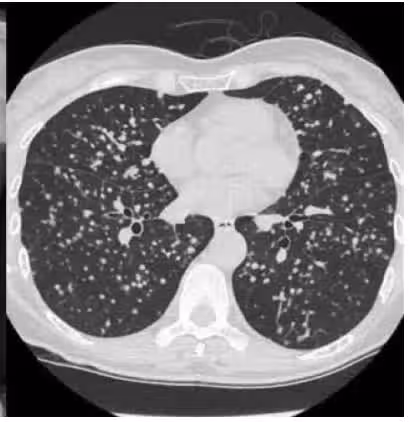

為了保持健康,陳醫師建議關注環境中的危險因素,比如二手煙、三手煙、空氣污染(如PM2.5、汽車廢氣等)、室內空氣污染(如廚房油煙、燒香等)以及遺傳基因等。至於肺癌的預防,陳醫師提出了三條建議:第一,遠離煙草,吸煙可縮短15年的壽命,戒煙後壽命會逐漸恢復;第二,減少有害物質的暴露,做飯時開啟抽油煙機,安裝熱交換器或空氣凈化器,注意空氣品質;第三,定期篩查。對於非高風險群體,建議考慮自費進行低劑量肺部CT檢查,因為早期肺癌往往無明顯症狀,早期發現能夠大大提高治療的成功率。陳醫師自己從35歲開始定期檢查,普通人建議從50歲開始檢查;有家族史等高風險群體,可以使用公共衛生資源進行篩查。